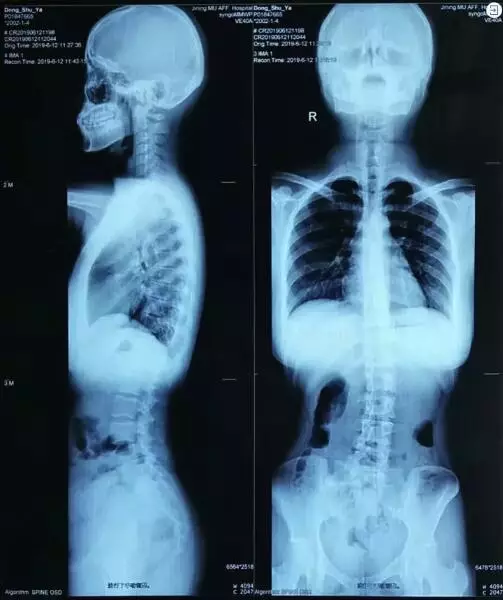

而導致這一情況的,是因為她存在脊柱側彎。

就這樣,萍萍就一直跟「脊柱側彎」共處,但因為脊柱側彎,她還出現了長短腿、腰骶處疼痛和僵硬、骨盆的前傾和側傾等問題。

「經過分析,萍萍的問題主要集中在腰骶部,腰骶僵硬,彎度較大。」浙江醫院康復治療中心治療師長湯洋說。

三維脊柱動態測試系統的結果顯示:7月初萍萍的脊柱右側側彎16度;訓練一個月後再次測試,脊柱恢復到接近7度。